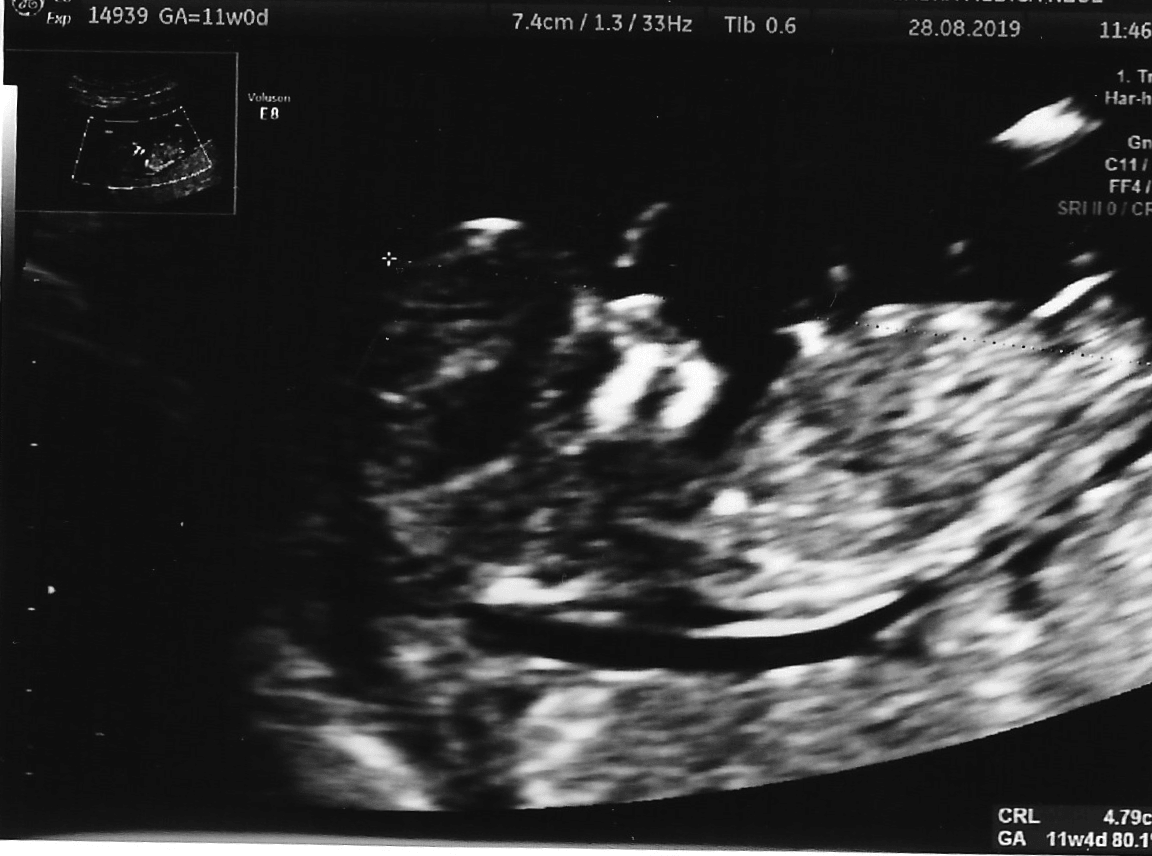

To był dokładnie 11 tydzień i 3 dzień. Zdjęcia niestety nie najlepszej jakości :/Czemu nie ocenia wstaw zobaczysz. A weź tu wklej usg tez

Ale ładnie widac buzialkaTo był dokładnie 11 tydzień i 3 dzień. Zdjęcia niestety nie najlepszej jakości :/